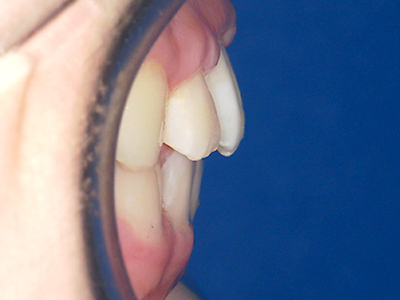

歯並びの相談に来られるお子様は、口呼吸をしているケースが多く、これが歯並びに大きな影響を与えています。

↓ - 下あごが狭くなる・下あごの位置が悪くなる

↓ - さまざまな不正咬合が生じる

ないき歯科クリニックでは、上あごの成長不足を補い、鼻呼吸を獲得しつつ歯列を整え、将来のお口をより健康な状態にすることをゴールに定める矯正治療をおこなっています。